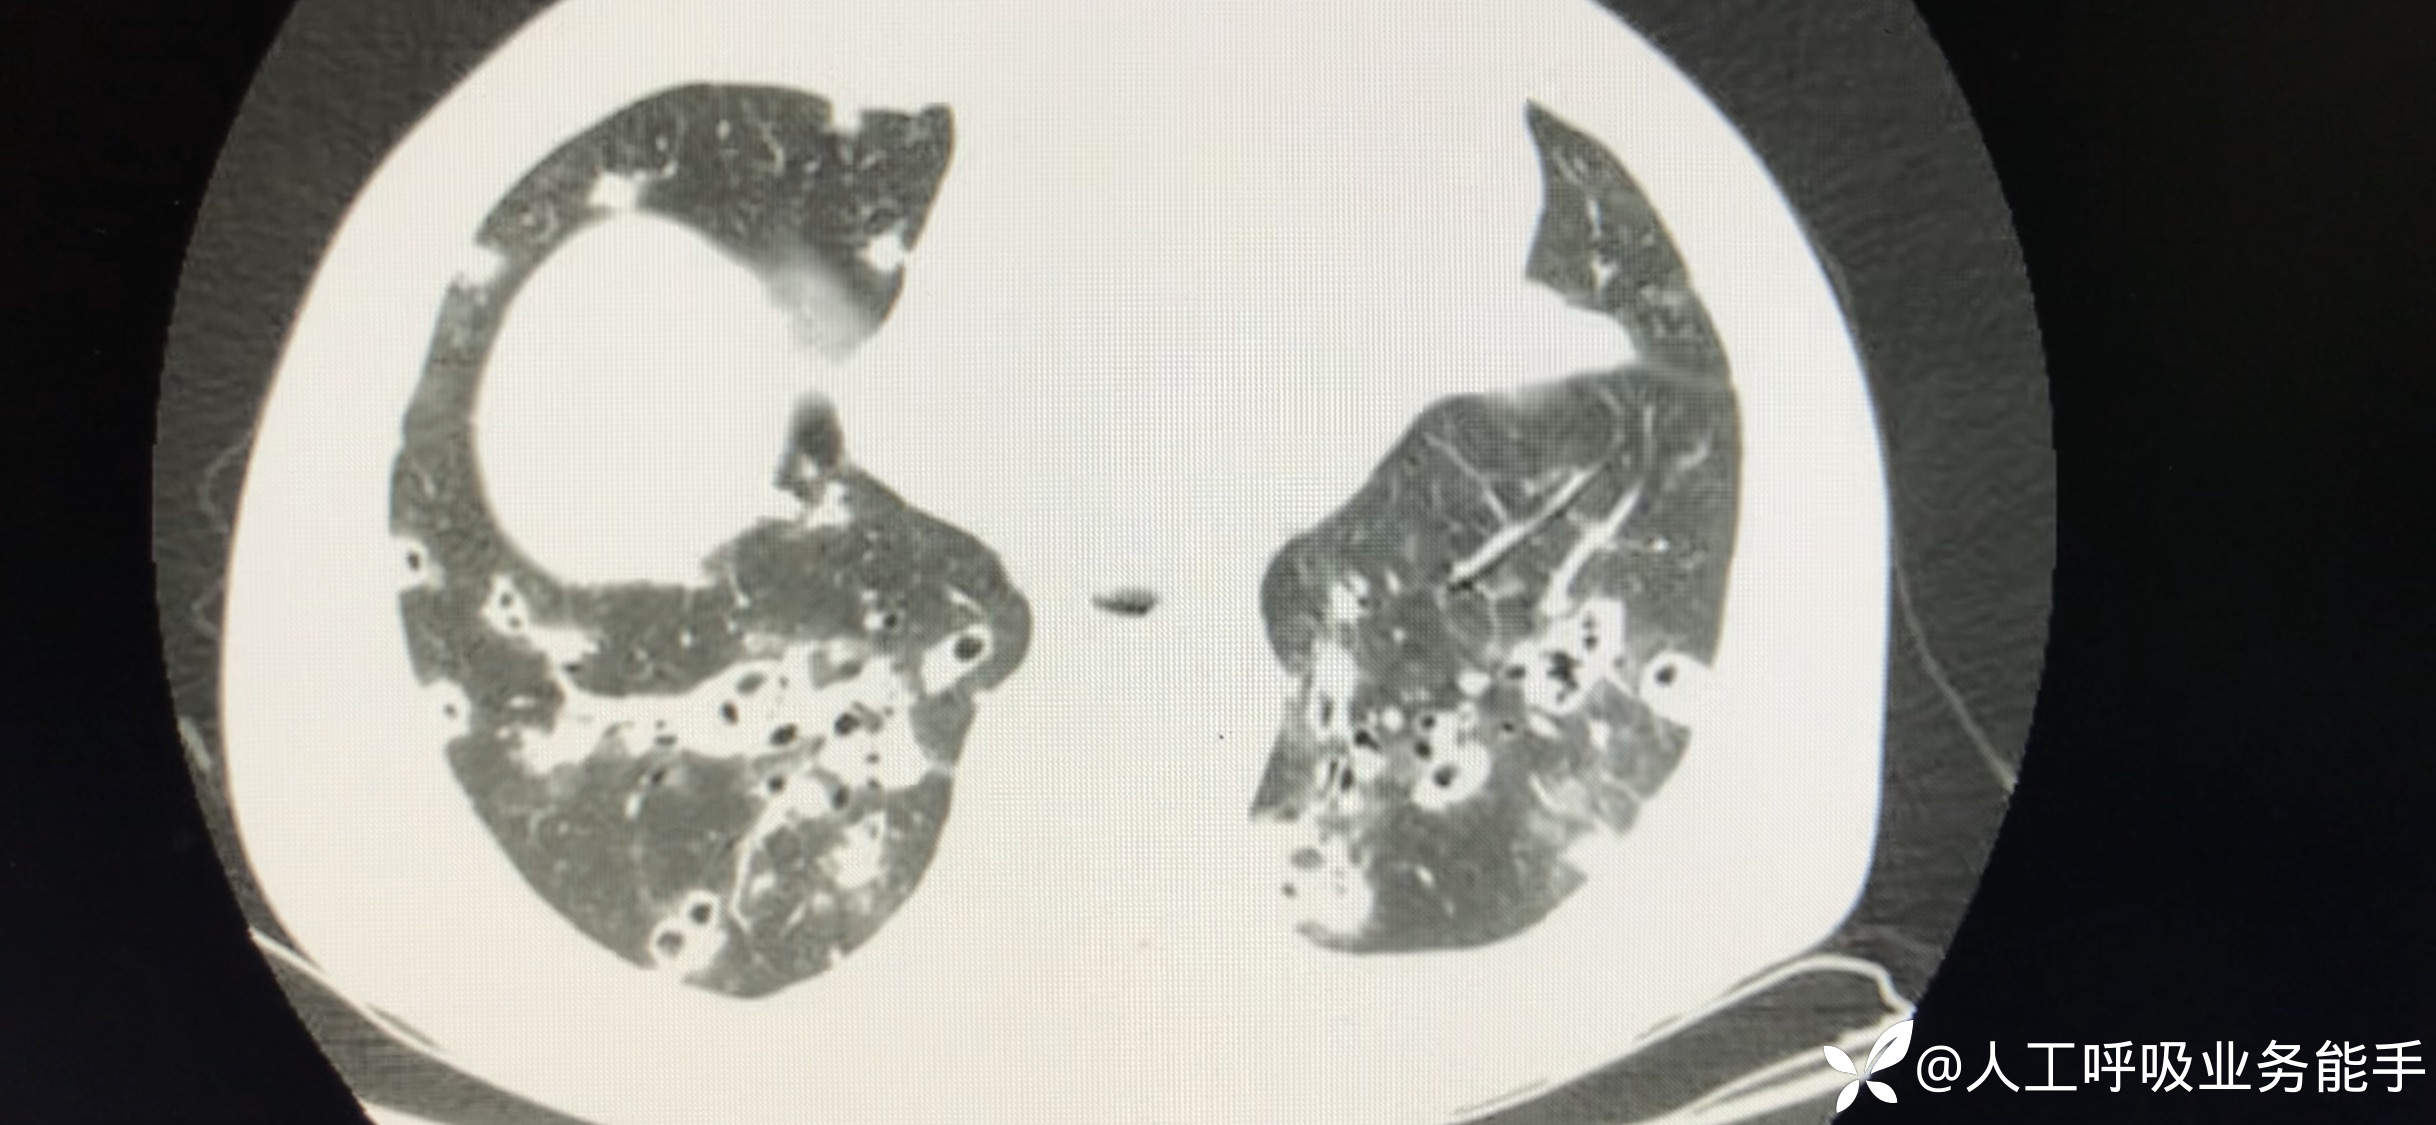

初诊影像: